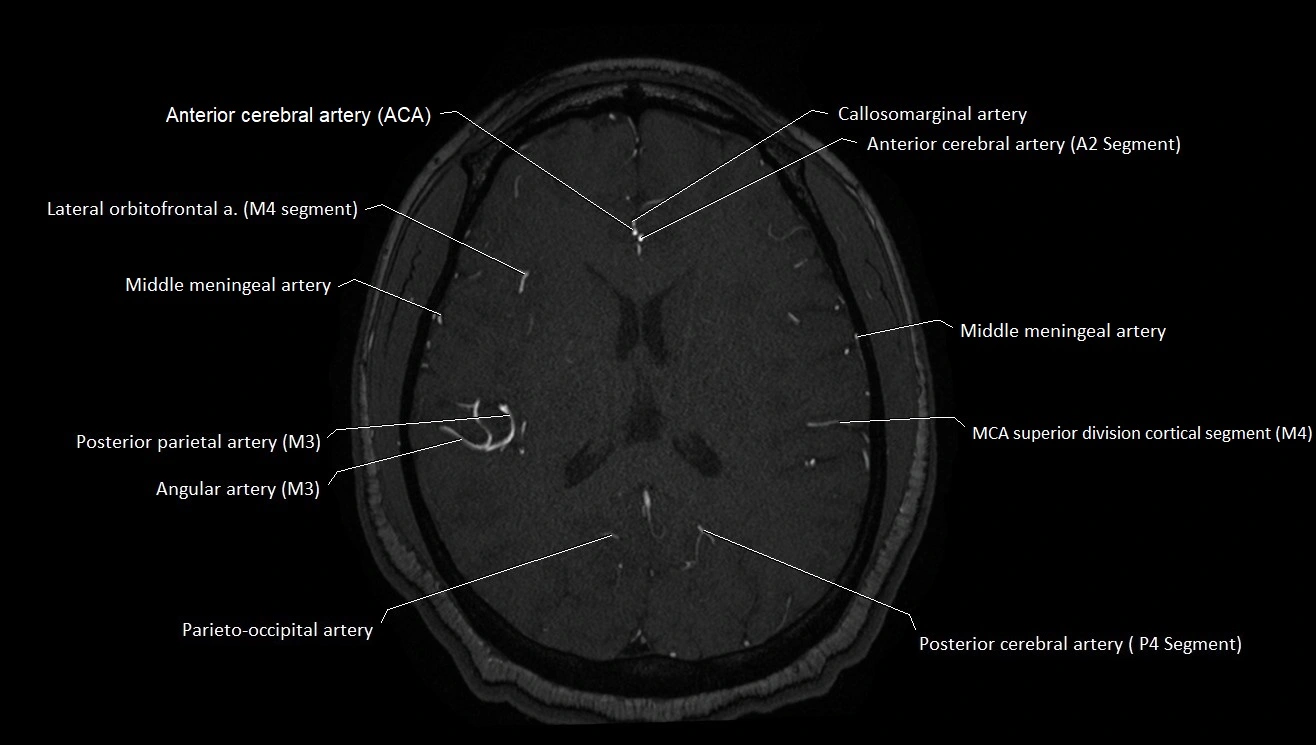

MRI images

image